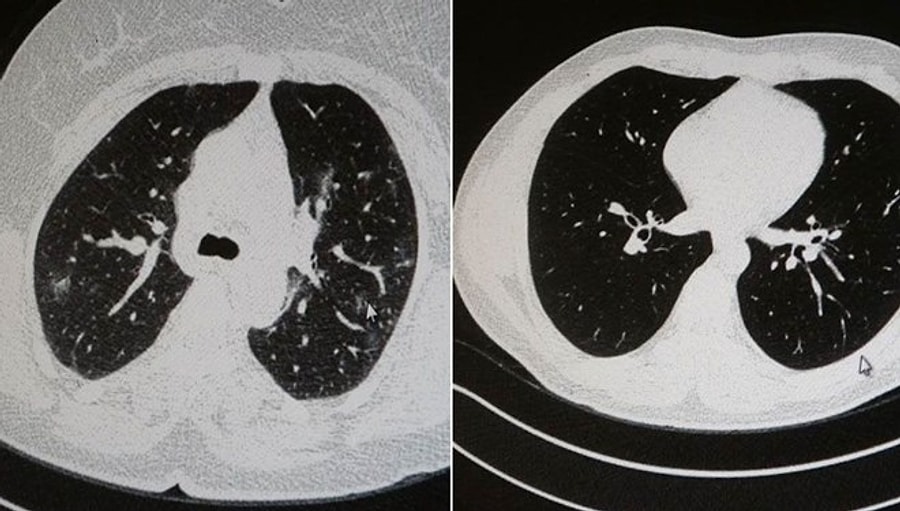

Görüntüler Korkutucu: Aşılı ve Aşısız Olarak Koronavirüse Yakalanan 2 Gencin Akciğer Tomografisi

Elazığ'da iki genç, öksürük, halsizlik, yorgunluk ve çabuk yorulma üzere şikayetlerle hastaneye başvurdu. Uzmanı Dr. Cebrail Azar, koronavirüs tespit edilen 2 genç hastadan aşısız olan ile aşılı olan ortasındaki farkı, tomografi sonuçlarında gösterdi.

Genç olduğu halde aşı olmayanlarda hastalığın ağır seyrettiğini tabir eden Uzm. Dr. Azar, 'Ben gencim, benim bağışıklık sistemim kuvvetli' diyen genç bir hastanın akciğerlerinde önemli lekelenmelerin olduğunu ve koronavirüs zatürresi olduğunu gördüklerini belitti.Uzm. Dr. Azar, tıpkı biçimde aşı olup koronavirüs hastalığına yakalanan bir öteki genç hastanın akciğer tomografisinde akciğerde rastgele bir sorunun olmadığını ve hastanın durumunun yeterli olduğunu gözlemlediklerini kaydetti.